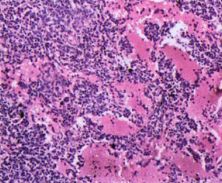

毛细胞白血病1例

图片尺寸575x411